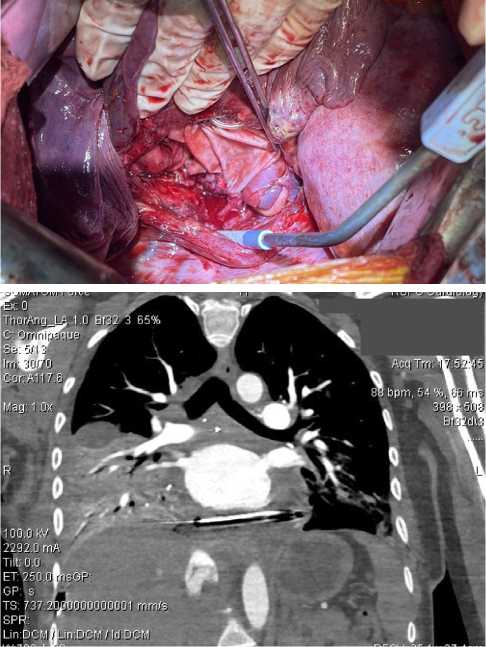

На втором этапе операции выполнен мультипортальный доступ справа. Начата мобилизация опухоли. Однако развилась десатурация до 75 %, которая потребовала перехода на двухлегочную вентиляцию и увеличения фракции кислорода во вдыхаемой смеси до 80 %. Заподозрена травма мембранозной части трахеи. Интраоперационно выполнена диагностическая фибробронхоскопия, травма исключена. Ввиду непереносимости однолегочной вентиляции продолжена двухлегочная ИВЛ, выполнена торакотомия справа. Произведено клипирование дренирующих опухоль вен в паратрахеальной области. При дальнейшей ревизии выявлена связь опухоли с задней стенкой левого предсердия (рис. 3). Для выполнения радикальной операции требовалась резекция левого предсердия в условиях искусственного кровообращения (ИК), что невозможно в условиях РНПЦ ОМР, в связи с чем операция была завершена. При манипуляциях с опухолью отмечались неоднократные подъемы артериального давления до 180/110 мм рт. ст и ЧСС до 120/мин, которые купировались в течение 5–10 мин. после прекращения манипуляций с опухолью.

Рис. 3. Инвазия опухоли в левое предсердие (интраоперационное фото)

Fig. 3. Tumor invasion into the left atrium (intraoperative photo)

На 3-и сутки после операции пациентка переведена в РНПЦ «Кардиология». Через 10 дней после первой операции совместной бригадой онко- и кардиохирургов в условиях ИК было выполнено удаление опухоли с резекцией и пластикой левого предсердия. Учитывая первичное выполнение частичной мобилизации опухоли из левосторонней ВАТС и правосторонней торакотомии, возможность подключения ИК различными способами, для выполнения операции был выбран доступ в виде правосторонней переднебоковой реторакотомии в 5-ом межреберье. Этот доступ также обеспечивает лучшую достижимость и практически полную визуализацию задней стенки ЛП, по сравнению со срединной стернотомией. Интраперикардиально и экстраперикардиально были мобилизованы легочные вены, правая легочная артерия, верхняя полая вена. Опухоль мобилизована от бифуркации трахеи, левого и правого главных бронхов с клипированием питающих сосудов диаметром до 2 мм. Затем стандартно был подключен АИК по схеме «правое предсердие — восходящая аорта». Операция выполнена в условиях нормотермической перфузии и кардиоплегии на основе крови. После остановки сердца устья правых легочных вен отсечены с площадкой ЛП, свободной от опухоли. Произведена резекция задней и верхней стенки левого предсердия с исходящей из нее опухолью с сохранением устьев левых легочных вен. Гиперваскуляризация опухоли, несмотря на предварительное клипирование основных питающих сосудов, потребовала дополнительного прошивания вен, дренирующих опухоль в проекции левого главного бронха. Для восстановления целостности левого предсердия было произведено его формирование «de novo» полотном ксеноперикарда крупного рогатого скота «Биокард» (СП ООО «Фармлэнд», РБ) обвивным непрерывным швом размером 5 × 6 см. Во вновь сформированном предсердии было выполнено отверстие 2 × 3 см, куда реимплантированы устья правых легочных вен. Самостоятельное восстановление сердечной деятельности после реперфузии. Длительность ишемии составила 134 мин., ИК — 190 мин. Пациентка экстубирована через 3 ч. после окончания операции, общий объем послеоперационной кровопотери в первые сутки составил 450 мл.

На 2 послеоперационные сутки диагностирована полисегментарная пневмония, которая разрешилась на 9 сут. Пациентка выписана на 10 сут. после операции. Объем левого предсердия и его функция адекватные, по результатам ЭХО-КГ и КТ-ангиографии (рис. 4).

Рис. 4. Вид после завершения реконструкции предсердия бычьим перикардом: А — интраоперационное фото; Б — КТА-ОГК после операции

Fig. 4. View after completion of atrial reconstruction with bovine pericardium: A — intraoperative photo; Б — postoperative thoracic CTA